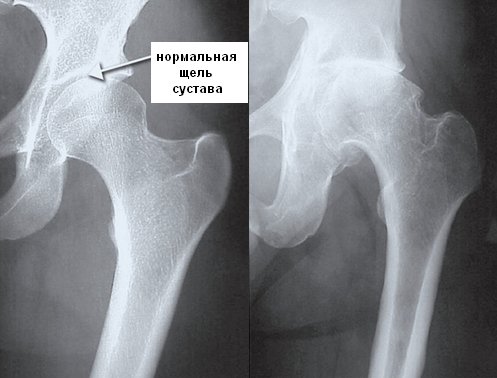

Результаты опроса и осмотра пациента имеют большое значение. Врач должен определить возможные факторы риска развития коксартроза. Основным методом диагностики остается рентгенография, которая позволяет выявить заболевание и оценить степень артроза. На рентгеновских снимках можно заметить следующие изменения:

- костные разрастания;

- сужение суставной щели;

- укорочение конечности;

- смещение головки кости;

- неровные контуры;

- увеличение головки бедра.